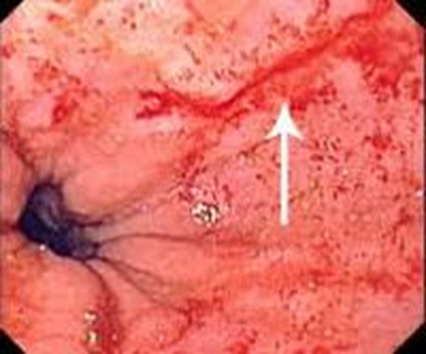

Эндоскопическая картина СМВ:

Комментарии: эндоскопическое исследование подтверждает наличие разрыва стенки пищевода и/или желудка, уточняет его локализацию, форму, размеры, глубину, наличие грыжи пищеводного отверстия диафрагмы и рефклюкс-эзофагита.